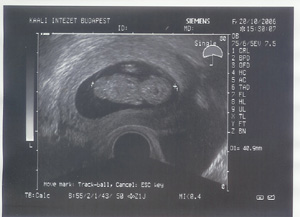

A te mensidnek viszont nagyon örülök. Drukkolok a mai vizsgálathoz. Az UH vizsgálatok nem ártanak a szervezetednek, emiatt ne félj. Még az sem igazolt, hogy a babának árt a sok UH.